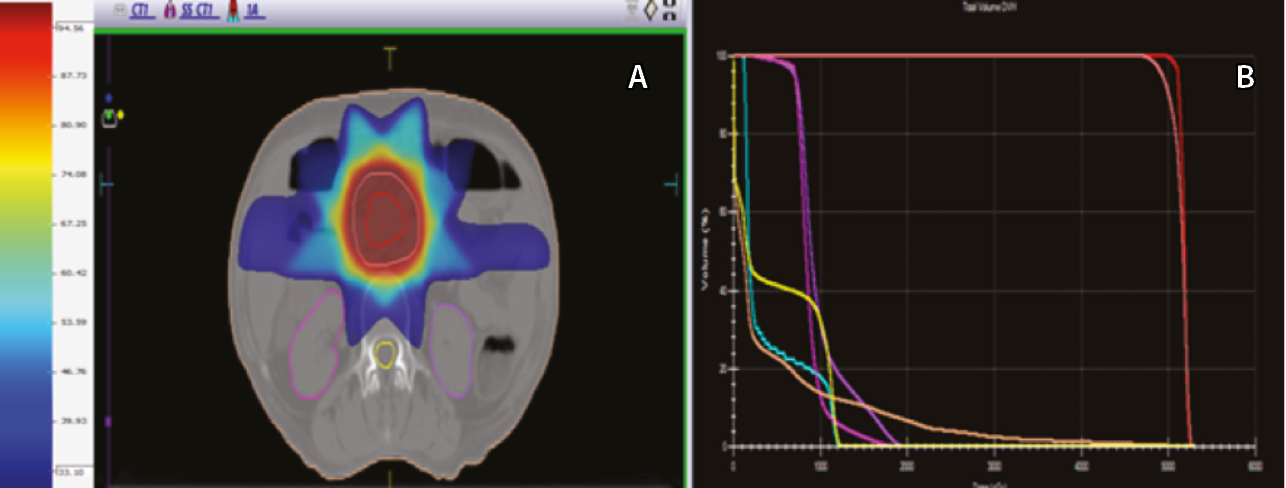

При проведении ангиографии использовали катетеры конфигурации hook или cobra (фирм Cook и Cordis, США или Terumo, Япония) размером 5 F. На ангиограммах из верхней брыжеечной артерии и чревного ствола определяли варианты сосудистой анатомии гепатопанкреатобилиарной зоны, источники кровоснабжения поджелудочной железы, состояние воротной вены по данным возвратной портографии. Затем осуществляли ангиографию общей, собственной печеночных и гастродуоденальной артерий (ГДА) для изучения ангиографических особенностей РПЖ, исключения или подтверждения метастатического поражения печени. Определяли оптимальное место установки катетера в положение, необходимое для проведения лечебного этапа процедуры (рис. 2).

Рис. 2. Ангиограммы пациентки Ш., 67 лет, диагноз: рак головки поджелудочной железы. Механическая желтуха купирована с помощью стентирования. А – при целиакографии отмечается один из вариантов сосудистой анатомии: замещающая левая печеночная артерия отходит от левой желудочной артерии (белая стрелка), правая и средняя – от общей печеночной артерии; пластиковый стент (черная стрелка) определяется в проекции холедоха. Б – катетер cobra 5 F установлен в общую печеночную артерию; коаксиально в правую желудочно-сальниковую артерию проведен микрокатетер 2,7 F, выполнена перераспределительная эмболизация металлической спиралью (черная стрелка); следующим этапом выполнена химиоэмболизация ветвей гастродуоденальной артерии, кровоснабжающих опухоль (белая стрелка). В – во время контрольной ангиографии из общей печеночной артерии отмечается накопление масляного препарата в опухоли (белая стрелка)